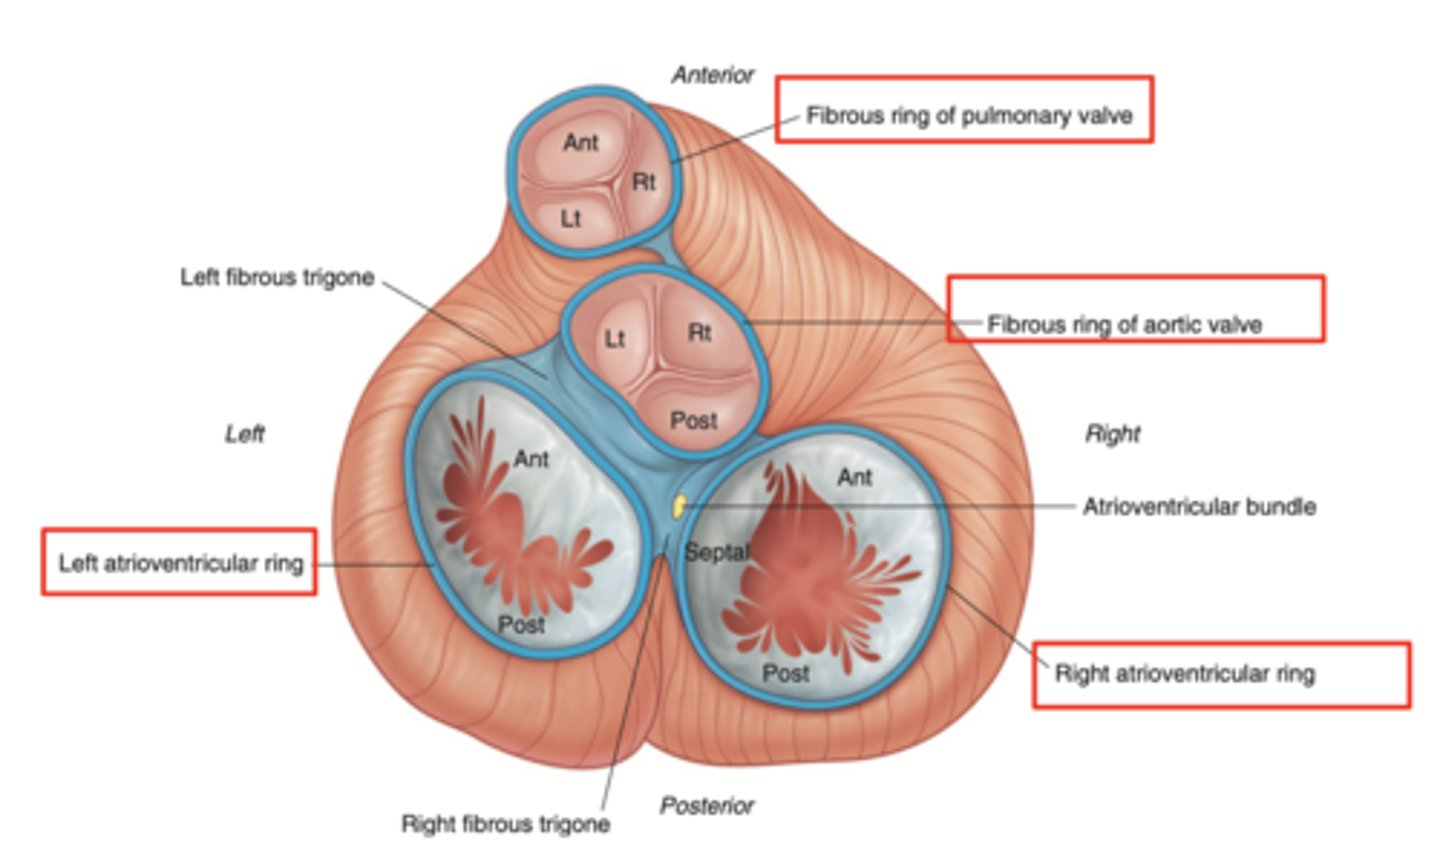

What are the valves separating atrium and ventricle?

. Tricuspid valve (right atrioventricular valve, 3 cusps)

. Mitral or bicuspid valve (left atrioventricular valve, 2 cusps)

AXIAL VIEW OF THE HEART

What are the four valves in the heart?

Tricuspid

Mitral or bicuspid

Pulmonary

Aortic

What are other functions of the rings in the cardiac skeleton?

maintain the shape of the openings between the heart's chambers

insertion site for the cusps of the valves and muscular heart tissue.

What are the components of the cardiac skeleton?

. pulmonary ring,

. aortic ring

. AV rings

RINGS ARE IN THE SAME PLANE AROUND THE VALVES